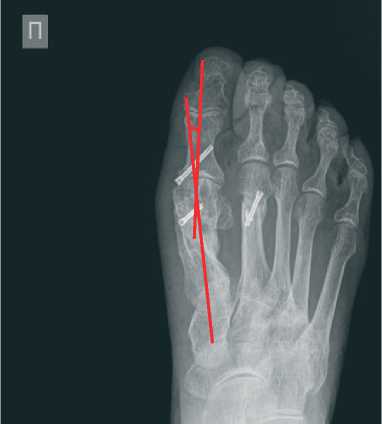

По данным стандартной рентгенографии стопы угол hallux valgus (М1Р1) исходно равен 45 градусов (Рисунок 2), угол ТО второго пальца – 45 градусов (Рисунок 3).

Рисунок 2. Исходные данные рентгенографии правой стопы в прямой проекции

По рентгенограмме в прямой проекции было подтверждено полное устранение hallux valgus (угол М1Р1= 7 градусов) (Рисунок 5). На снимке в боковой проекции угол ТО был равен 30 градусов (Рисунок 6).

Рисунок 5. Данные рентгенографии правой стопы в прямой проекции через 1 год после операции